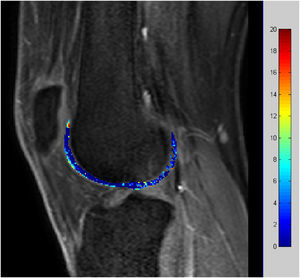

Imágenes del realce tardíoEn los estudios de RM adquiridos tras la administración de un medio de contraste, éste se distribuye lentamente en el interior del cartílago. Aproximadamente a las 2 h de su administración, y habiendo andado el paciente durante al menos 10 min, su distribución en el cartílago es inversamente proporcional a la concentración de proteoglicanos y glucosaminoglicanos.

Conocida como dGEMRIC (delayed gadolinium-enhanced MRI of cartilage), se basa en el hecho de que el contraste con carga eléctrica negativa se distribuirá en aquellas regiones que presenten una menor concentración de glucosaminoglicanos y proteoglicanos, o en donde estén dañados13,14. Es por esto que las imágenes paramétricas de los T1, directamente proporcionales a la cantidad local de contraste, pueden considerarse como indicadores de la concentración de estas macromoléculas. Dado que los proteoglicanos son críticos para mantener las propiedades mecánicas de la matriz cartilaginosa y se alteran precozmente con la degeneración, esta técnica es un biomarcador temprano y eficaz para diagnosticar la enfermedad y seguir la eficacia del proceso terapéutico.

Dado que el contraste tiene una carga negativa, será rechazado por los proteoglicanos que también tienen carga eléctrica negativa. Aquellas zonas con una menor proporción de proteoglicanos retienen más este contraste, y su distribución se visualiza con precisión mediante la cuantificación de los T1 longitudinal del cartílago. Se ha demostrado que en la degeneración del cartílago se produce precozmente un daño a la matriz colágena de proteoglicanos12.